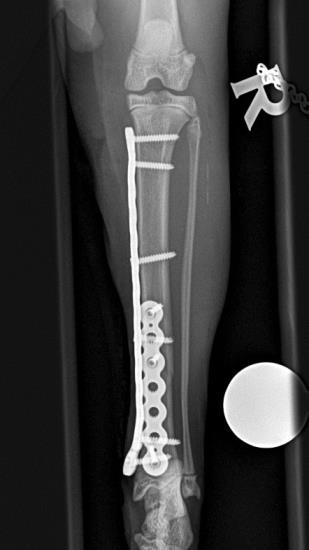

These radiographs show a distal tibial fracture in a six-month cat. Multiple fissure lines can be seen extending towards the distal tibial physis. The tibia is a common site of non-union in the cat and plate failure by bending following tibial fracture stabilisation is reported. In this case, an orthogonal plate has been applied to the cranial aspect of the tibia. This not only allows increased construct stiffness in the sagittal plane but provides for an additional screw fixation point. This can be very useful with distal fractures.

The cat, in this case, was allowed early ambulation and went on to make a full recovery. The PAX advanced locking system is well suited to cat fracture repairs such as this.